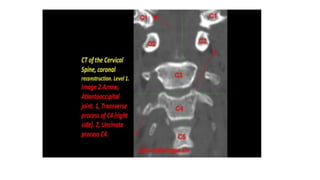

This three-dimensional CT model is oriented with the observer looking cephalad along the anterior

surface of the cervical spine. A series of holes perforating the transverse processes of each vertebra

can be seen—the transverse foramen.

This three-dimensional CTmodel is oriented with the observer looking cephalad along the anterior surface of the cervical spine. A series of holes perforating the transverse processes of each vertebra can be seen—the transverse foramen.